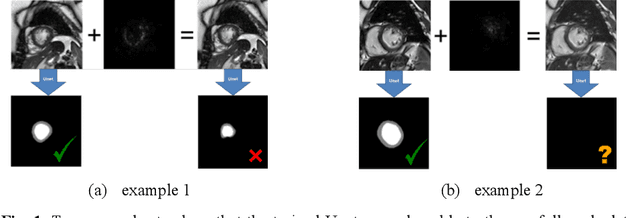

Abstract:Convolutional neural network (CNN), in particular the Unet, is a powerful method for medical image segmentation. To date Unet has demonstrated state-of-art performance in many complex medical image segmentation tasks, especially under the condition when the training and testing data share the same distribution (i.e. come from the same source domain). However, in clinical practice, medical images are acquired from different vendors and centers. The performance of a U-Net trained from a particular source domain, when transferred to a different target domain (e.g. different vendor, acquisition parameter), can drop unexpectedly. Collecting a large amount of annotation from each new domain to retrain the U-Net is expensive, tedious, and practically impossible. In this work, we proposed a generic framework to address this problem, consisting of (1) an unpaired generative adversarial network (GAN) for vendor-adaptation, and (2) a Unet for object segmentation. In the proposed Unet-GAN architecture, GAN learns from Unet at the feature level that is segmentation-specific. We used cardiac cine MRI as the example, with three major vendors (Philips, Siemens, and GE) as three domains, while the methodology can be extended to medical images segmentation in general. The proposed method showed significant improvement of the segmentation results across vendors. The proposed Unet-GAN provides an annotation-free solution to the cross-vendor medical image segmentation problem, potentially extending a trained deep learning model to multi-center and multi-vendor use in real clinical scenario.